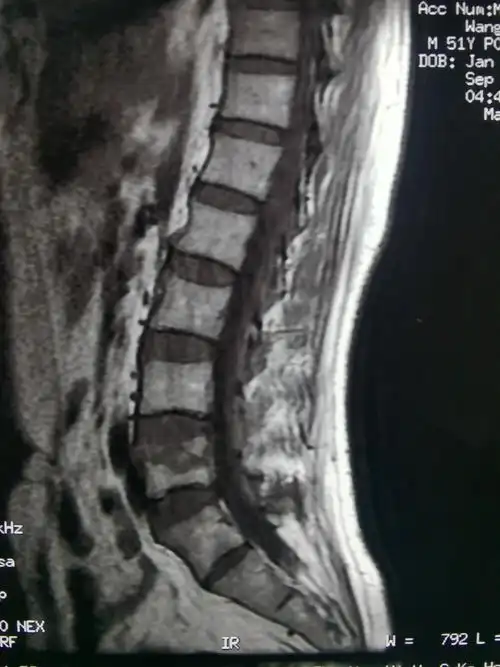

术前腰椎mri平扫t1图像